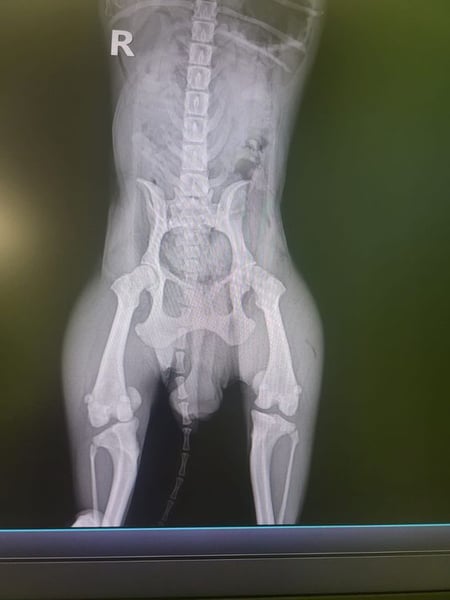

Bemerkungen: Bei Carmen entwickelt sich auf beiden Augen ein Hornhautgeschwür, das medikamentös behandelt wird. Sie hat Osteoporose im linken Hüftgelenk, der linke Rippenbogen wurde operiert und drei Zähne entfernt. Beim Röntgen wurde eine Verschattung der kranialen Bronchien festgestellt, und sie hat eine anbeborene Fehlbildung der Kniescheiben.

Carmen verbrachte ihr Leben in einer Vermehrerstation. Sie wurde den Tierschützern angeboten, und wir denken, dass diese „freundliche“ Geste dann doch wohl eher mit dem gesundheitlichen Zustand von Carmen zusammenhängt. Bei Carmen entwickelt sich auf beiden Augen ein Hornhautgeschwür. Als medizinische Anwendung bekommt Carmen momentan 2 x täglich Corneregel. Ferner hat sie Osteoporose im linken Hüftgelenk. Ihr wurden drei Zähne entfernt und der linke Rippenbogen operiert. Der Thorax wurde geröntgt und eine Verschattung der kranialen Bronchien festgestellt, ferner eine angeborene Fehlbildung der Kniescheiben.